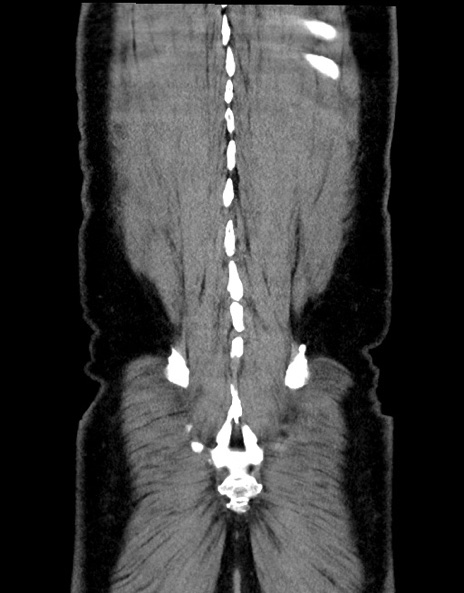

症例15(冠状断像)

横断像